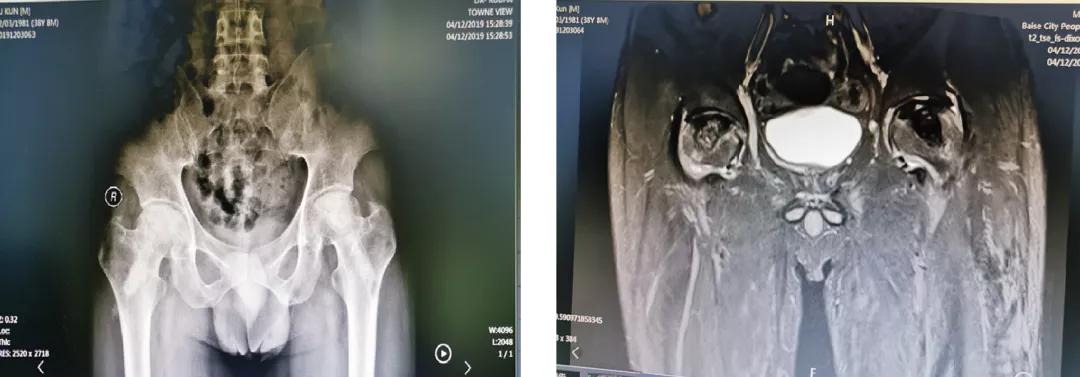

案例二

35岁的覃先生,也是双侧股骨头坏死,经同事介绍到关节与运动医学科住院,选择左侧人工全髋关节置换术、右侧机器人辅助下保髋治疗,术后效果良好,患者及其家属非常满意。

术前辅助检查

右侧保髋、左侧THA